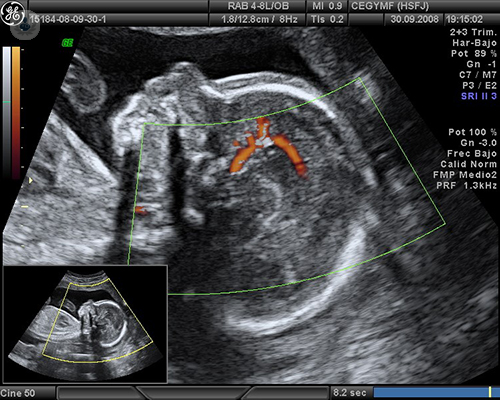

La Ecografía Doppler color en el control fetal

El Dr. Gorostiaga Ruiz-Garma explica en qué consiste una ecografía Doppler, en qué casos se recomienda su uso y cuáles son sus aplicaciones de cara al control del embarazo.

Ecografía doppler en embarazos de riesgo

La ecografía doppler es una forma de ecografía en color avanzada. La información que aporta es muy útil para conocer el estado y crecimiento del feto. El Dr. Pakzad, experto en Ginecología y Obstetricia, informa de que se recomienda en embarazos de riesgo o en madres con determinadas patologías.